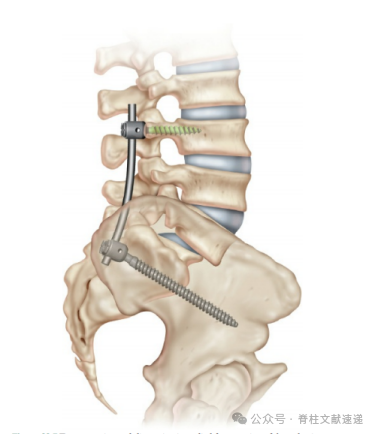

3.腓骨销技术

在L5和S1椎体之间置入异体腓骨销来提高融合率,是一种良好的技术。向尾端切除部分骶骨椎板,显露S1和S2神经根间隙,进针点S1椎体中线外侧1cm处和S1~S2椎间盘水平,S1和S2神经根之间。透视或导航引导下2mm克氏针穿过L5~S1椎间隙和L5椎体,不穿过L5前皮质,前交叉韧带(ACL)铰刀做出通道,比人工腓骨直径小1mm,撤出铰刀后打入人工腓骨销,可单侧,也可双侧植入,可显著提高L5-S1融合率。同时进行后外侧融合。